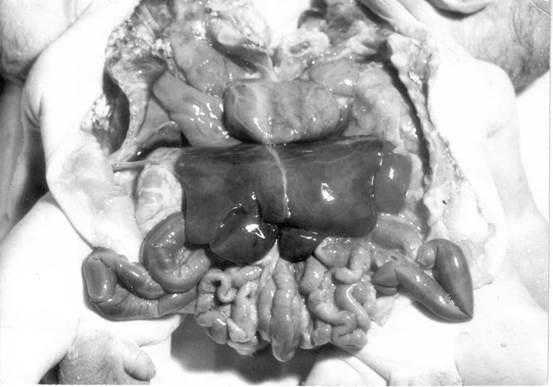

В раннем эмбриональном периоде грудные и брюшные органы располагаются по средней линии. В норме ротация и рост происходит вправо, а при situs viscerus inversus – влево. Situs viscerus inversus обычно наблюдается у сросшихся близнецов (рис.1). Эта аномалия крайне редко встречается у остальных людей (1 на 8000-25000 новорожденных) [14].

Рис.1. Внутренние органы торакоабдоменопагусов. Видна одна печень, одно сердце, один желудок, но кишечник у каждого близнеца раздельный.